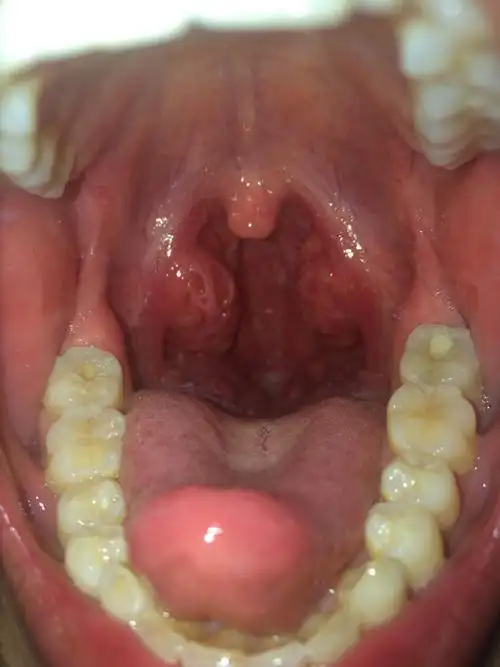

喉咙长得东西好像滤泡咽喉炎,干痒,咳嗽.

没症状. 之前急性咽喉炎. 吃药好了.

扁桃体本来有的,喉咙这个样子怎么了,左侧有点不舒服